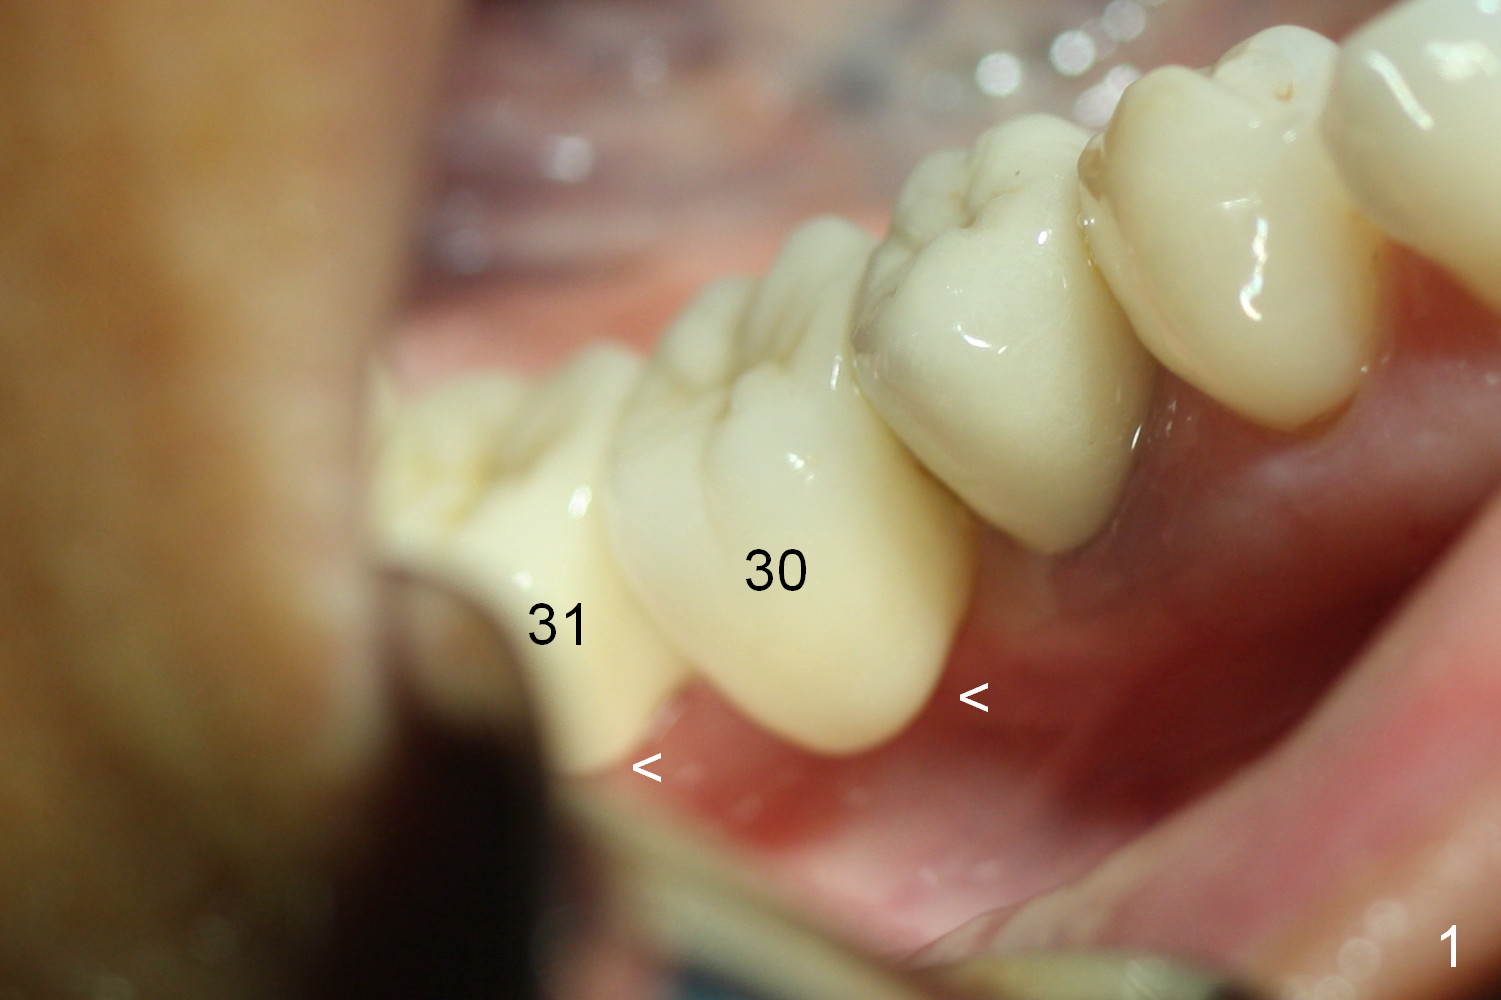

A preop photo shows different shape of pontics at #30 and 31 (Fig.1 <), suggesting different width of the edentulous ridge. Two of 8 mm parallel pins are inserted for position and trajectory (Fig.2 (red dashed line: the superior border of the Inferior Alveolar Canal). When they are removed from the osteotomy sites, the narrow ridge at #30 is shown (Fig.3). A 3x12 mm 1-piece implant is placed at #30, while a 4.5x10 mm 2-piece one at #31 (Fig.4,5). It appears that it is necessary to place an implant at #32, since the tooth #1 is present (Fig.5). The suggestion is rejected by the patient due to finance. After extraction of the tooth #32 and insertion of collagen plug, an immediate splinted provisional is fabricated to cover the #32 socket as well (Fig.6). The provisional is modified (to remove the portion that covers #32 socket) 3-4 weeks postop.

The patient returns for final restoration 3 months postop; bone resorption around the 1-piece implant is minimal (Fig.7). The definitive restoration is also splinted. The latter is further justified when the implant at #30 is found to be distal prior to cementation (Fig.8 *). It appears that implant spacing at the root level is more critical than parallelism, as compared to Fig.7. Let us improve this aspect. Bone loss around the implants remains minimal 7 months post cementation (Fig.9). It is the same 1 year 8 months post cementation (Fig.10), as compared to a cantilever FPD on the other side (Fig.11). The bone density around the implants at #30 and 31 increases 2 year 8 months post cementation (Fig.12).